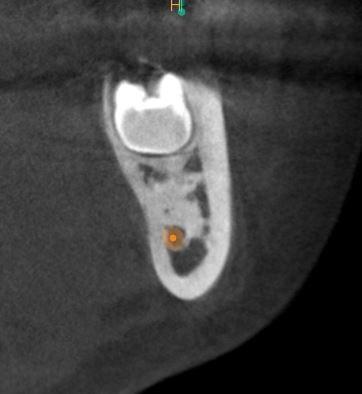

CBCT wycinkowe żuchwy. Okolica 38.

Ząb 38 częściowo zatrzymany ,położony skośnie w kierunku dystalnej powierzchni zęba 37.

Mezjalnie od zęba 38 ,okolica 37 i przesrzeni międzyzębowej 37/38 widoczny obszar zacienienia o charakterze „matowego szkła". Obrys kości niezmieniony.